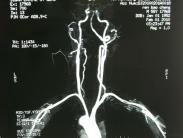

鎖骨下動脈盜血綜合征癥狀

• 鎖骨下動脈盜血綜合征

628健康網為您分享有關鎖骨下動脈盜血綜合征的癥狀,鎖骨下動脈盜血綜合征的治療方法,鎖骨下動脈盜血綜合征的預防知識...